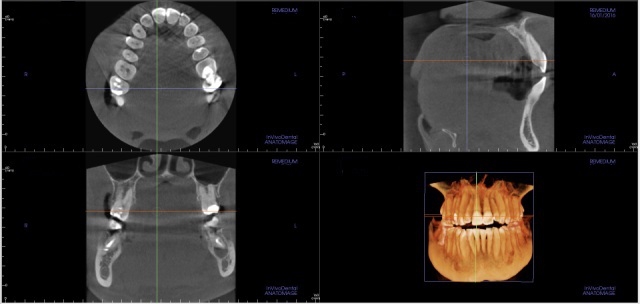

Tomografia

to zaawansowane badanie obrazowe, które wykonuje się m.in. w diagnostyce zębów oraz zatok przynosowych. Dostarcza bardzo szczegółowych danych, które mogą być cyfrowo przetworzone na trójwymiarowe obrazy. Jest wyjątkowo przydatna we współczesnej endodoncji, niezbędna w planowaniu leczenia implantologicznego oraz projektowaniu uśmiechu w protetyce stomatologicznej.